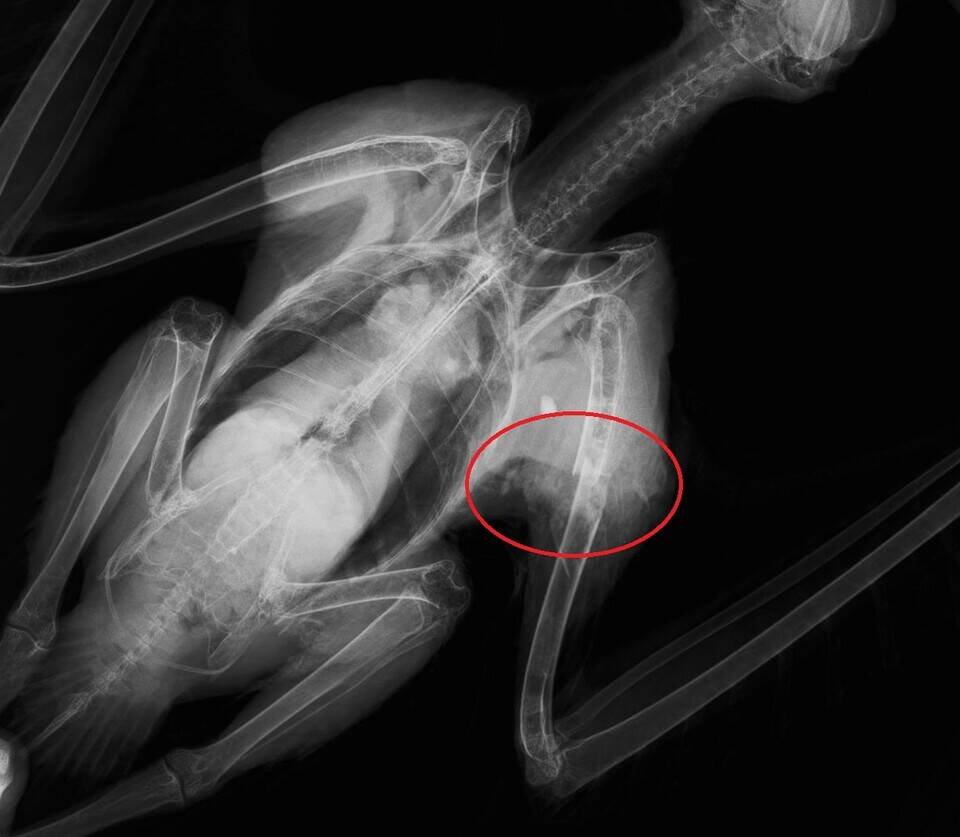

赤丸の部位の骨は横向きにポキッっと折れているので横骨折と言います。